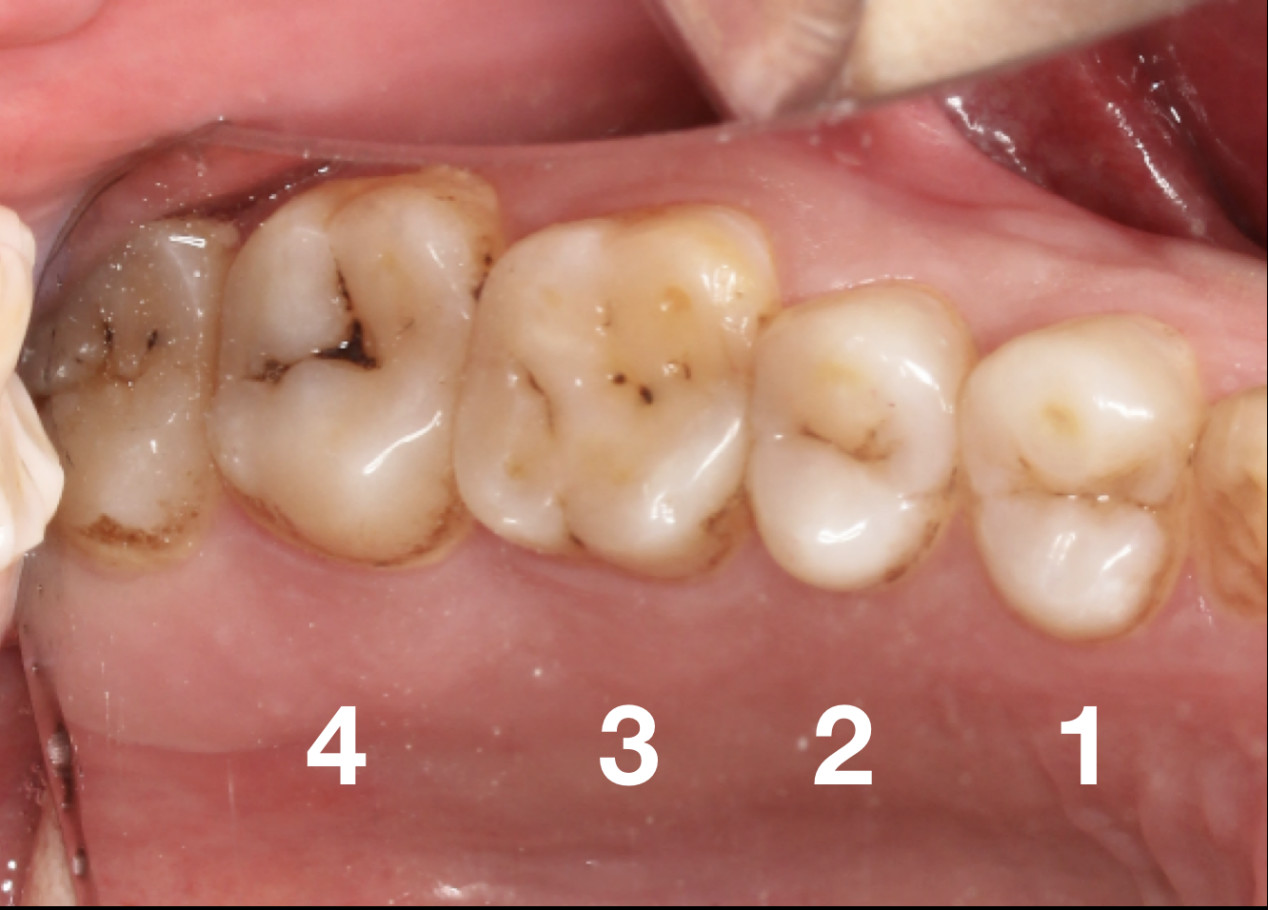

初期我们很难发现被细菌“盯”上的牙齿,等牙疼了才能明白,原来小黑线、黑块是龋齿(蛀牙)的表现。

想要知道到底是龋齿,还是色素沉着,还是比较难分辨的。但色素沉着一般会导致多颗牙齿被染色,染色是比较均匀的。

而蛀牙一般只有一两颗牙齿会显示出黑线。但是当色素牙和蛀牙同时出现时,我们就很难辨别出来了,只能通过医疗设备X-光检查。

浅龋。牙齿表面有黑线,最表层牙釉质被破坏,初步形成蛀牙。

中龋。龋坏加重,牙齿第二层牙本质被破坏。遇冷热酸甜食物牙齿会敏感,冷刺激尤为明显,可出现疼痛反应,当刺激源去除后疼痛立即消失。

深龋。龋坏到达牙本质深层,一般表现为大而深的龋洞,或入口小而深层有较为广泛的破坏。对外界刺激反应比中龋重,但刺激源去除后,仍可立即止痛,无自发性痛。